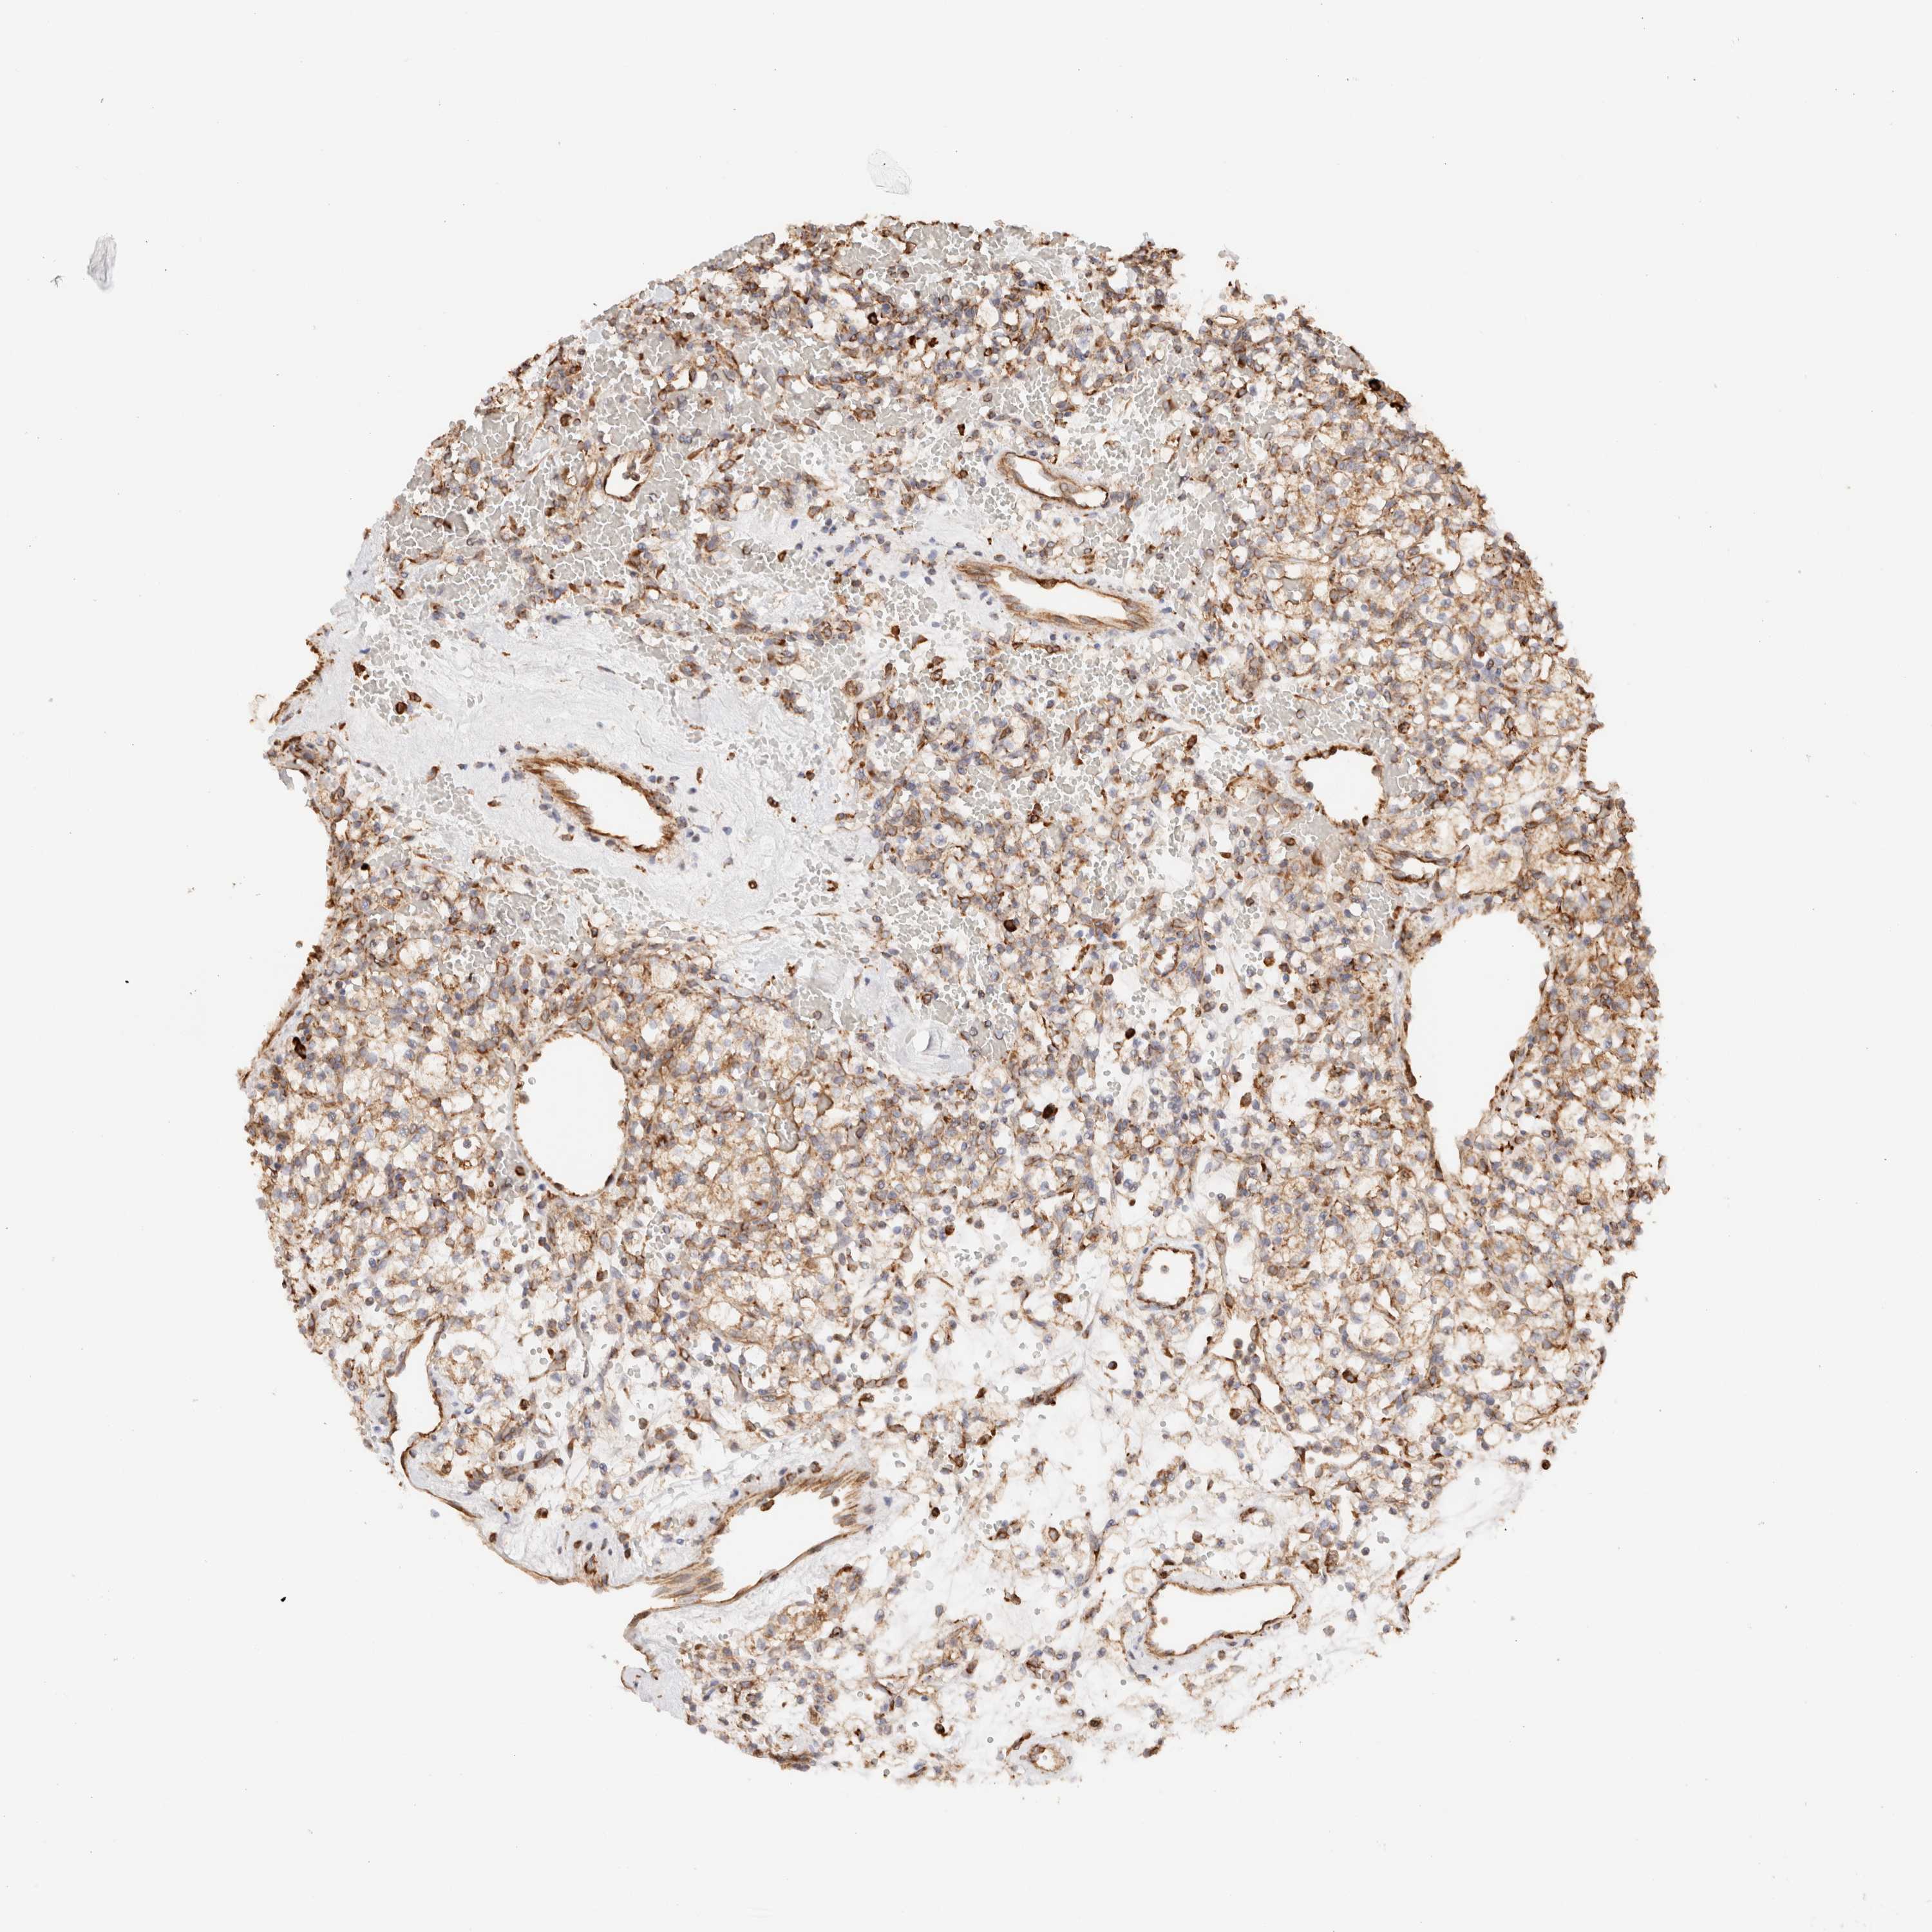

KIDNEY RENAL CLEAR CELL CARCINOMA (TCGA) - Interactive survival scatter ploti

The Survival Scatter plot shows the clinical status (i.e. dead or alive) for all individuals in the patient cohort, based on the same data that underlies the corresponding Kaplan-Meier plots. Patients that are alive at last time for follow-up are shown in blue and patients who have died during the study are shown in red.

The x-axis shows the expression levels (FPKM) of the investigated gene in the tumor tissue at the time of diagnosis. The y-axis shows the follow-up time after diagnosis (years). Both axes are complimented with kernel density curves demonstrating the data density over the axes. The top density plot shows the expression levels (FPKM) distribution among dead (red) and alive patients (blue). The right density plot shows the data density of the survived years of dead patients with high and low expression levels respectively, stratified using the cutoff indicated by the vertical dashed line through the Survival Scatter plot. This cutoff is automatically defined based on the FPKM cutoff that minimizes the p-score. The cutoff can be changed by dragging the vertical line or by entering a cutoff value in the square labeled "Current cut-off".

Under the Survival Scatter plot the p-score landscape (black curve; left axis) is shown together with dead median separation (red curve; right axis). Dead median separation is the difference in median mRNA expression between patients who have died with high and low expression, respectively. It is calculated as follows: median FPKM expression of dead patients with high expression - median FPKM expression of dead patients with low expression. This is intended to aid the user in visually exploring custom cutoffs and the associated p-scores and dead median separation.

Individual patient data is displayed and can be filtered by clicking on one or more of the category buttons on the top of the page. Categories describing expression level and patient information include: high, low, alive, dead, female, male and tumor stages. The scale of the x-axis can be toggled between linear and log-scale by clicking on the "x log" button. Mouse-over function shows TCGA ID, patient information and mRNA expression (FPKM) for each patient.

& Survival analysisi

Kaplan-Meier plots summarize results from analysis of correlation between mRNA expression level and patient survival. Patients were divided based on level of expression into one of the two groups "low" (under cut off) or "high" (over cut off). X-axis shows time for survival (years) and y-axis shows the probability of survival, where 1.0 corresponds to 100 percent.

FER is potential prognostic, high expression is favorable in Kidney Renal Clear Cell Carcinoma (TCGA)

Best expression cut offi

: 3.12

P scorei

N/A

Average pTPM 3.2

Number of samples 521